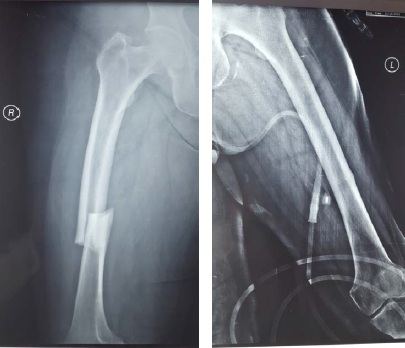

According to the newest guidelines of the ASBMR (American Society of Bone and Mineral Research), the patient underwent intramedullary nailing of the right femur and was instructed to discontinue bisphosphonate along with non-weight bearing of the left lower extremity [17-19]. Although a bone scan was conducted for further investigation of the incomplete fracture and the presence of other imperfect fracture sites, no new lesions were found (Figures 2 and 3). After 6 weeks, there was a clinical improvement in the left femur and radiographic appearance of callus, thus excluding the prophylactic intramedullary nailing of the left femur. The union of both fractures developed normally both for the right femur which was treated with intramedullary nailing and the left femur where conservative treatment was selected. The union of the right femur was not affected by the fact that the distal locking screw was not centered in the nail hole. The radiographic monitoring of the bone healing was conducted at 3, 6 and 12 months after the first treatment took place (Figures 4 and 5).

Figure 5. AP radiograph of both femoral shafts 1-year after surgery